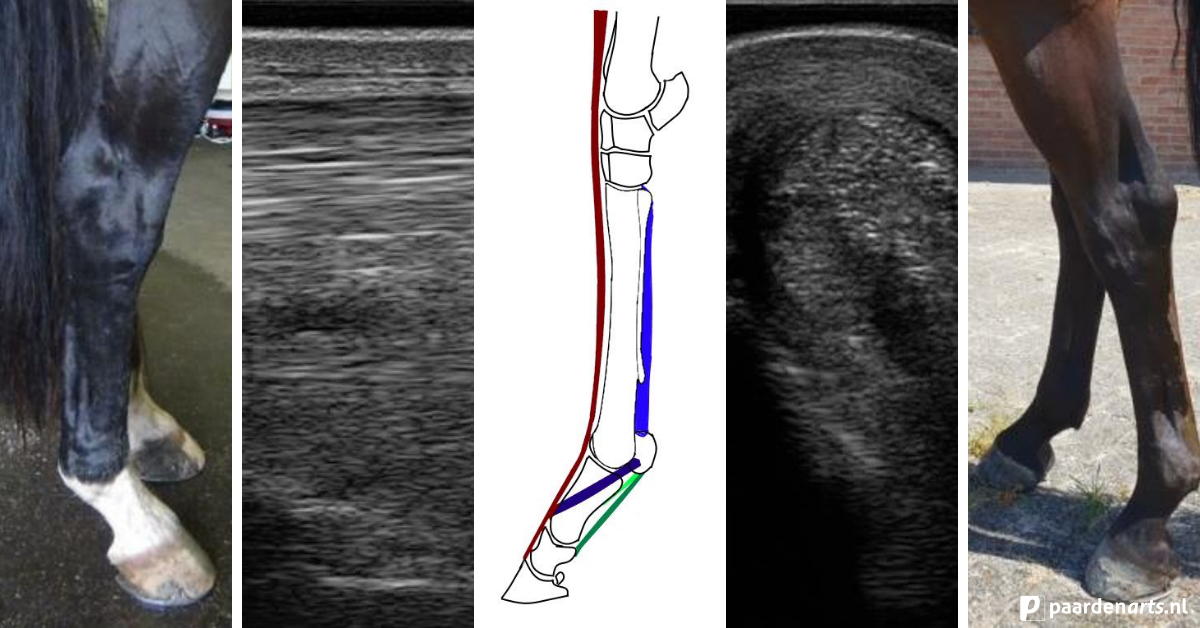

Om te kunnen begrijpen waarom en hoe blessures aan de tussenpees ontstaan is het nodig iets van de anatomie van de tussenpees te weten. De tussenpees ligt ingesloten tussen het pijpbeen, de griffelbeentjes en de diepe buigpees (met checkligament), vandaar ook zijn naam. We kunnen de tussenpees onderverdelen in drie delen:

Ter hoogte van het midden van de pijp splitst de pees namelijk in twee takken die dan elk aan een sesambeentje vasthecht ter hoogte van de kogel. Van hieruit loopt hij verder naar de voorkant van het kootbeen waar hij versmelt met de strekpees (zie afb. 1).

Er zijn anatomische verschillen tussen de tussenpees in het voorbeen en het achterbeen. Onder andere de vorm, de ligging, de vetgedeeltes en de spiergedeeltes verschillen hierbij. Daarnaast heeft het achterbeen een stevig vliesje, een zogenoemde fascie. Deze fascie loopt over de tussenpees van het ene griffelbeentje naar het andere. Daarnaast loopt er bij het achterbeen een specifieke zenuw naar de aanhechting van de tussenpees.